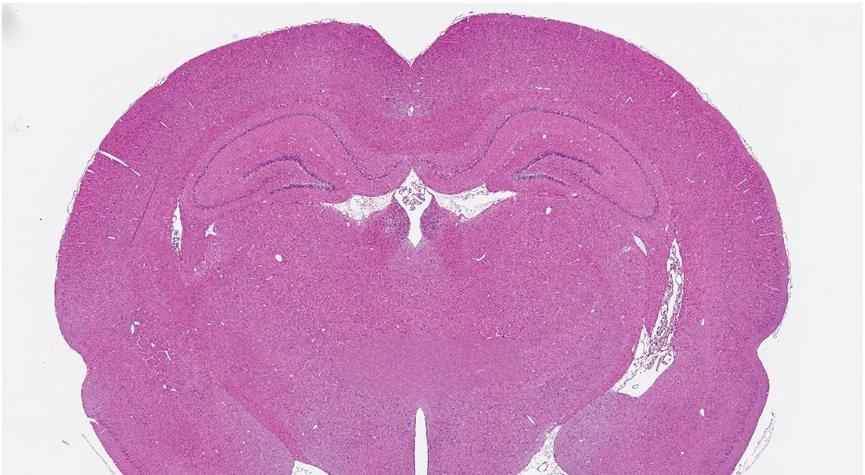

石蜡切片HE染色全流程详解 ?HE染色,即苏木精-伊红染色法,是病理切片中的常规染色方法。其原理在于组织或细胞的不同成分对苏木精色素的亲和力不同,经染色后细胞核及钙盐粘液等呈现蓝色,而胞浆及其他成分则呈现深浅不同的红色。 步骤如下: 固定:离体后的组织应及时进行固定,常用固定液有中性福尔马林、4%多聚甲醛等。固定液与组织体积比最好为10:1,固定时长一般为24-48小时。 脱水:利用梯度酒精对固定完全的组织进行脱水,为包埋剂的浸入做准备。具体操作包括75%酒精溶液30分钟--85%酒精溶液60分钟--95%酒精60分钟--100%酒精I 60分钟--100%酒精II 60分钟。 透明:二甲苯置换酒精,为包埋剂的浸入做第二步处理。具体操作包括二甲苯I 30分钟--二甲苯II 30分钟。 浸蜡:石蜡I 60分钟--石蜡II 60分钟--石蜡III 60分钟。 包埋:将组织固定于包埋剂中,便于切片。目前大多有模具,可根据实验所需进行正确包埋。 切片:使用切片机对埋块切片,一般厚度为3-4um。切片前,可提前将埋块放入冰水中浸泡,避免组织切片出现裂痕。 染色: 脱蜡:二甲苯I 15分钟--二甲苯II 15分钟--100%酒精I 5分钟--100%酒精II 5分钟--95%酒精5分钟--75%酒精5分钟----纯水。 染色:苏木素4分钟--自来水冲洗--分化液分化3秒--自来水冲洗--返蓝液显蓝1分钟--自来水充分冲洗5~10分钟--伊红25秒~1分钟。 脱水透明:80%乙醇40秒--95%乙醇1分钟--无水乙醇I 5分钟--无水乙醇II 5分钟--二甲苯I 5分钟--二甲苯II 10分钟--二甲苯III 10分钟。 封片:中性树脂封片,待其自然晾干后即可置于显微镜下观察拍照。 注意:片子不可在空气中长时间暴露,会有水分进入,因此从二甲苯取出后应迅速封片,不然将影响后续观察拍照。 发自小木虫手机客户端 |